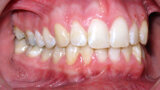

ClearCorrect treatment of crowding